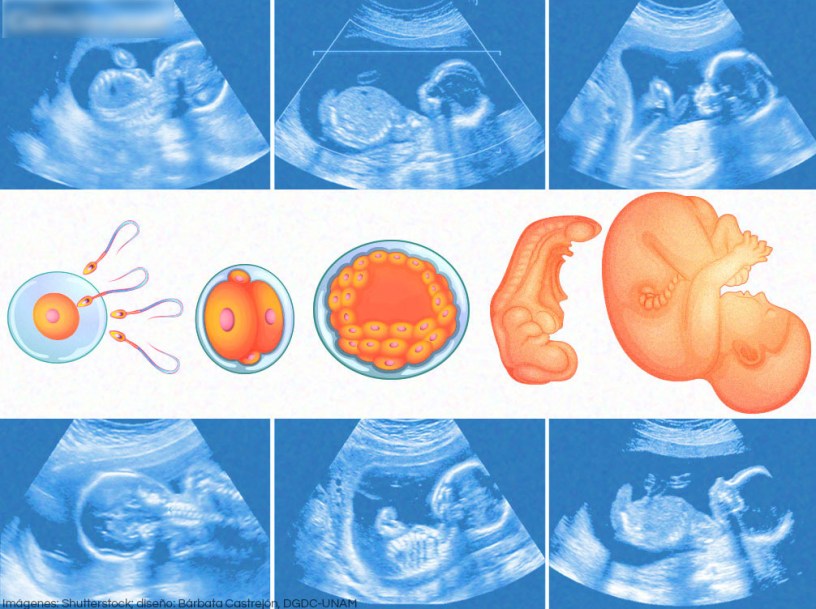

| EMBRIOLOGIA\ (10) | 1.185 | ||

| Atlas de Embriologia Humana – Netter – 1era Edición.pdf | 256 | 327 | PDFdemo |

| Embriologia Clinica – Arteaga – 1era Edición.pdf | 596 | 347 | PDFdemo |

| Embriologia Clinica – Moore – 9na Edición.pdf | 559 | 63 | PDFdemo |

| Embriología Humana – Armando Valds – 1era Edición.pdf | 283 | 20 | PDFdemo |

| Embriologia Humana – Flores – 1era Edición.pdf | 575 | 143 | PDFdemo |

| Embriologia Humana y Biologia del Desarrollo – Carlson – 5ta Edición.pdf | 521 | 58 | PDFdemo |

| Embriologia Medica – Langman – 13ra Edición.pdf | 241 | 95 | PDFdemo |

| Embriologia Medica – Langman – 8va Edición.pdf | 426 | 120 | PDFdemo |

| Embryology – High Yield – 5th Edition.pdf | 172 | 12 | PDFdemo |

| Histologia y Embriologia – DOcttavio – 2da Edición.pdf | 223 | 1 | PDFdemo |